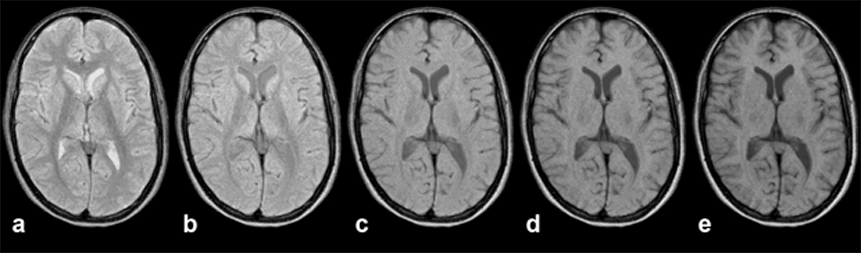

Figure 10-13:

Gradient echo pulse sequence (spoiled GRE) through the brain of a patient with a vascular mal­for­ma­tion in the right occipital hemisphere.

The upper image series was ta­ken with an echo time TE = 20 ms, the lower series with an echo time TE = 120 ms (B₀ = 1.5 T). The lesion is nearly invisible in the image series with short TE, but well de­li­ne­at­ed in the series with long TE.

The choice of the appropriate pulse se­quen­ce parameters is pivotal in MR ima­ging. Many different sequences can be applied for different diagnostic questions. In many instances, their contrast behavior has been recorded empirically and the se­quen­ce and specific sequence pa­ra­me­ters have been included in special clinical ima­ging protocols.

As we have seen in the SE se­quen­ces, one can hide and miss pathological chan­ges by choosing the wrong pulse se­quen­ce. This also holds for rapid se­quen­ces. If we se­lect a T1-weighted se­que­nce, we cannot distinguish a lesion which possesses a si­mi­lar T1 to its neighboring tissues. If we apply a T2*-weighted sequence, we cannot de­li­ne­ate a lesion with a T2 close to the T2 of its surroundings. The signal intensity of the vascular malformation in Figure 10-13 is a good example of this problem.